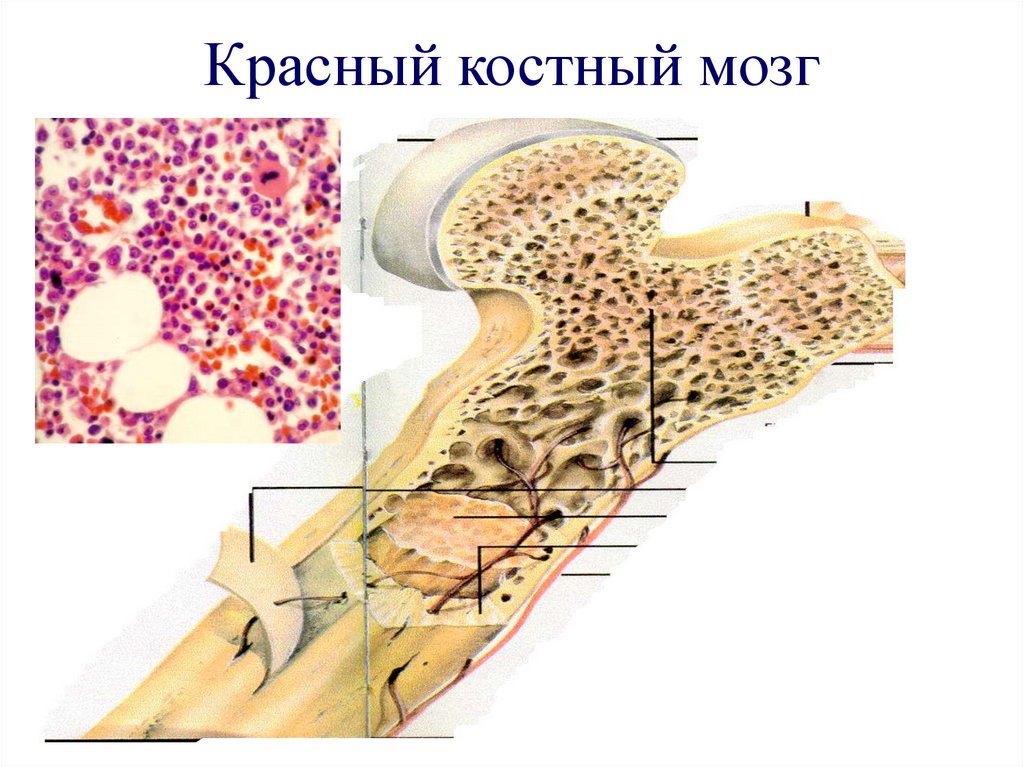

Изучение костного мозга: анатомия и функции